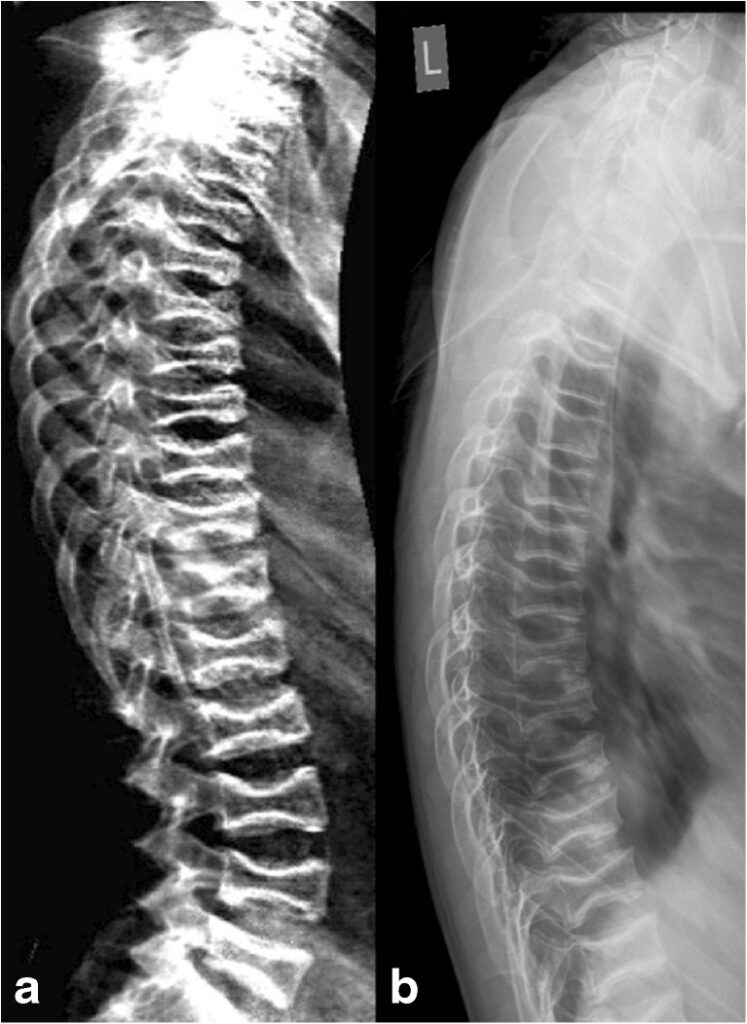

Questa tecnica si avvale di radiografie standard del rachide toracico e lombare eseguite in proiezione laterale. La MRX è storicamente considerata il “gold standard” per la sua eccellente risoluzione spaziale, che permette non solo la misurazione geometrica ma anche una valutazione qualitativa delle limitanti somatiche e degli spazi intervertebrali.5

Tuttavia, la MRX presenta limiti tecnici non trascurabili. La divergenza del fascio radiogeno può causare distorsioni geometriche e il fenomeno della parallasse, rendendo difficile la precisa individuazione dei bordi vertebrali, specialmente in presenza di scoliosi. Inoltre, richiede che il paziente sia posizionato con estrema cura per garantire che i corpi vertebrali siano perfettamente paralleli al piano sensibile, onde evitare la proiezione di “doppi contorni” delle limitanti somatiche che invaliderebbero la misurazione.

Vertebral Fracture Assessment (VFA/MXA)

La VFA viene eseguita utilizzando la tecnologia Dual-energy X-ray Absorptiometry (DEXA), la stessa impiegata per la misurazione della densità ossea. Questa tecnica ha guadagnato rapidamente terreno nella pratica clinica grazie alla sua praticità e sicurezza. Molti sistemi moderni utilizzano una tecnologia a raggio a ventaglio (fan-beam) con un braccio rotante che acquisisce l’immagine laterale del paziente in posizione supina, eliminando gran parte delle distorsioni geometriche tipiche della radiologia conica.6

Nonostante questi vantaggi, la VFA soffre di una risoluzione spaziale inferiore, il che può rendere difficoltosa la visualizzazione delle vertebre toraciche superiori (sopra T6) a causa della sovrapposizione delle scapole e del tessuto polmonare.7 Per questo motivo, in presenza di sospetti clinici forti o deformità complesse, la radiologia convenzionale o la risonanza magnetica rimangono strumenti di approfondimento necessari.